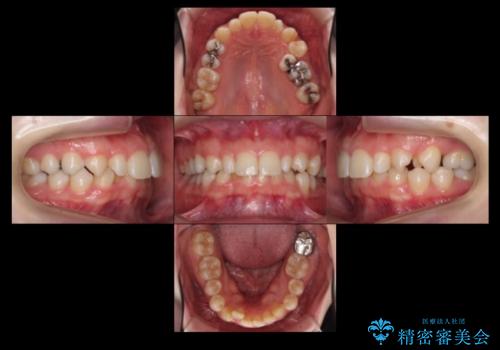

- 前歯を整えたいと来院。

左右の前から2番目の歯が細く、矮小でした。

また、奥歯が2つ並んでおり歯ブラシがしにくい状態でした。

内側に入っている左上5を抜歯しています。

抜歯したスペースを使い、歯並びを整え、さらにその隙間を利用して細い歯を大きく整えてセラミックで被せるという総合的な治療を行いました。

マウスピース矯正→上顎両側2番のセラミック、左下67の虫歯治療 の順で行いました。